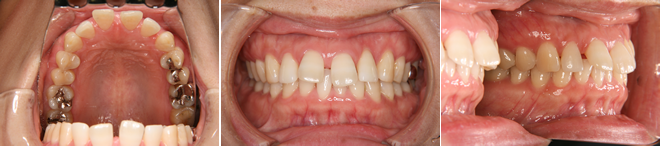

| 主訴 | 前歯が出ている |

| 年齢・性別 | 35歳 / 女性 |

| 治療方針 | 叢生も前歯の突出も大きいケース。小臼歯抜歯だけでは改善できないため、大臼歯の抜歯も行なった。 |

| 抜歯部位 | 上下顎左右小臼歯、左上第1大臼歯(計5本) |

| 使用装置 | マルチブラケット装置 |

| 治療期間 | 36か月 |

| リテーナー | 上顎インビジブル、フィックス、下顎インビジブル |

| 費用 | 885,000円(税別) |